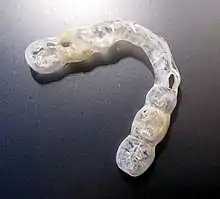

Devices

Occlusal splints (also termed bite plates or intra-oral appliances) are often used by dentists to treat TMD. They are usually made of acrylic and can be hard or soft. They can be designed to fit onto the upper teeth or the lower teeth. They may cover all the teeth in one arch (full coverage splint) or only some (partial coverage splint). Splints are also termed according to their intended mechanism, such as the anterior positioning splint or the stabilization splint.[18] Although occlusal splints are generally considered a reversible treatment,[48] sometimes partial coverage splints lead to pathologic tooth migration (changes in the position of teeth). Normally splints are only worn during sleep, and therefore probably do nothing for people who engage in parafunctional activities during wakefulness rather than during sleep. There is slightly more evidence for the use of occlusal splints in sleep bruxism than in TMD. A splint can also have a diagnostic role if it demonstrates excessive occlusal wear after a period of wearing it each night. This may confirm the presence of sleep bruxism if it was in doubt. Soft splints are occasionally reported to worsen discomfort related to TMD.[18] Specific types of occlusal splint are discussed below.

A stabilization splint is a hard acrylic splint that forces the teeth to meet in an "ideal" relationship for the muscles of mastication and the TMJs. It is claimed that this technique reduces abnormal muscular activity and promotes "neuromuscular balance". A stabilization splint is only intended to be used for about 2–3 months.[17] It is more complicated to construct than other types of splint since a face bow record is required and significantly more skill on the part of the dental technician. This kind of splint should be properly fitted to avoid exacerbating the problem and used for brief periods of time. The use of the splint should be discontinued if it is painful or increases existing pain.[68] A systematic review of all the scientific studies investigating the efficacy of stabilization splints concluded the following:

"On the basis of our analysis we conclude that the literature seems to suggest that there is insufficient evidence either for or against the use of stabilization splint therapy over other active interventions for the treatment of TMD. However, there is weak evidence to suggest that the use of stabilization splints for the treatment of TMD may be beneficial for reducing pain severity, at rest and on palpation, when compared to no treatment".[17]

Partial coverage splints are recommended by some experts, but they have the potential to cause unwanted tooth movements, which can occasionally be severe. The mechanism of this tooth movement is that the splint effectively holds some teeth out of contact and puts all the force of the bite onto the teeth which the splint covers. This can cause the covered teeth to be intruded, and those that are not covered to over-erupted. I.e. a partial coverage splint can act as a Dahl appliance. Examples of partial coverage splints include the NTI-TSS ("nociceptive trigeminal inhibitor tension suppression system"), which covers the upper front teeth only. Due to the risks involved with long term use, some discourage the use of any type of partial coverage splint.[18]

An anterior positioning splint is a splint that designed to promote an anteriorly displaced disc. It is rarely used.[18] A 2010 review of all the scientific studies carried out to investigate the use of occlusal splints in TMD concluded:

"Hard stabilization appliances, when adjusted properly, have good evidence of modest efficacy in the treatment of TMD pain compared to non-occluding appliances and no treatment. Other types of appliances, including soft stabilization appliances, anterior positioning appliances, and anterior bite appliances, have some RCT evidence of efficacy in reducing TMD pain. However, the potential for adverse events with these appliances is higher and suggests the need for close monitoring in their use."[70]